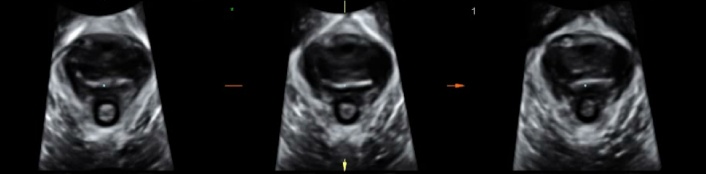

经过细致的盆底超声检查,医生确认王阿姨脱出来的“肿块”主要是膀胱的后壁,也就是所谓的Green III型膀胱脱垂;同时经过三维超声检查,王阿姨的耻骨直肠肌也没有明显的撕脱。根据超声结果,我院盆底疾病中心的医生为王阿姨定制了个性化的盆底治疗方案,现在王阿姨再也没有“肿块”的困扰了。

(缩肛状态盆膈裂孔三维成像)